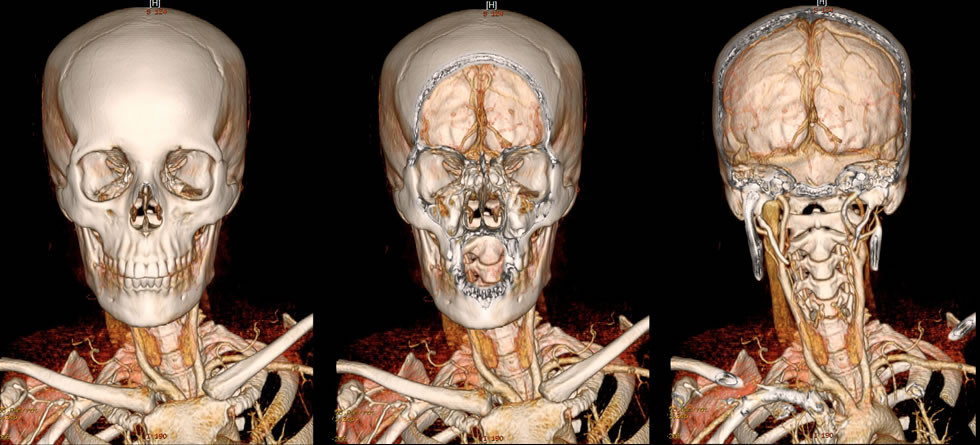

Interpretación de Estudios Especiales

La realización de reconstrucciones y secuencias especiales en Tomografía y Resonancia magnética, como angioTC con r...

Leer más